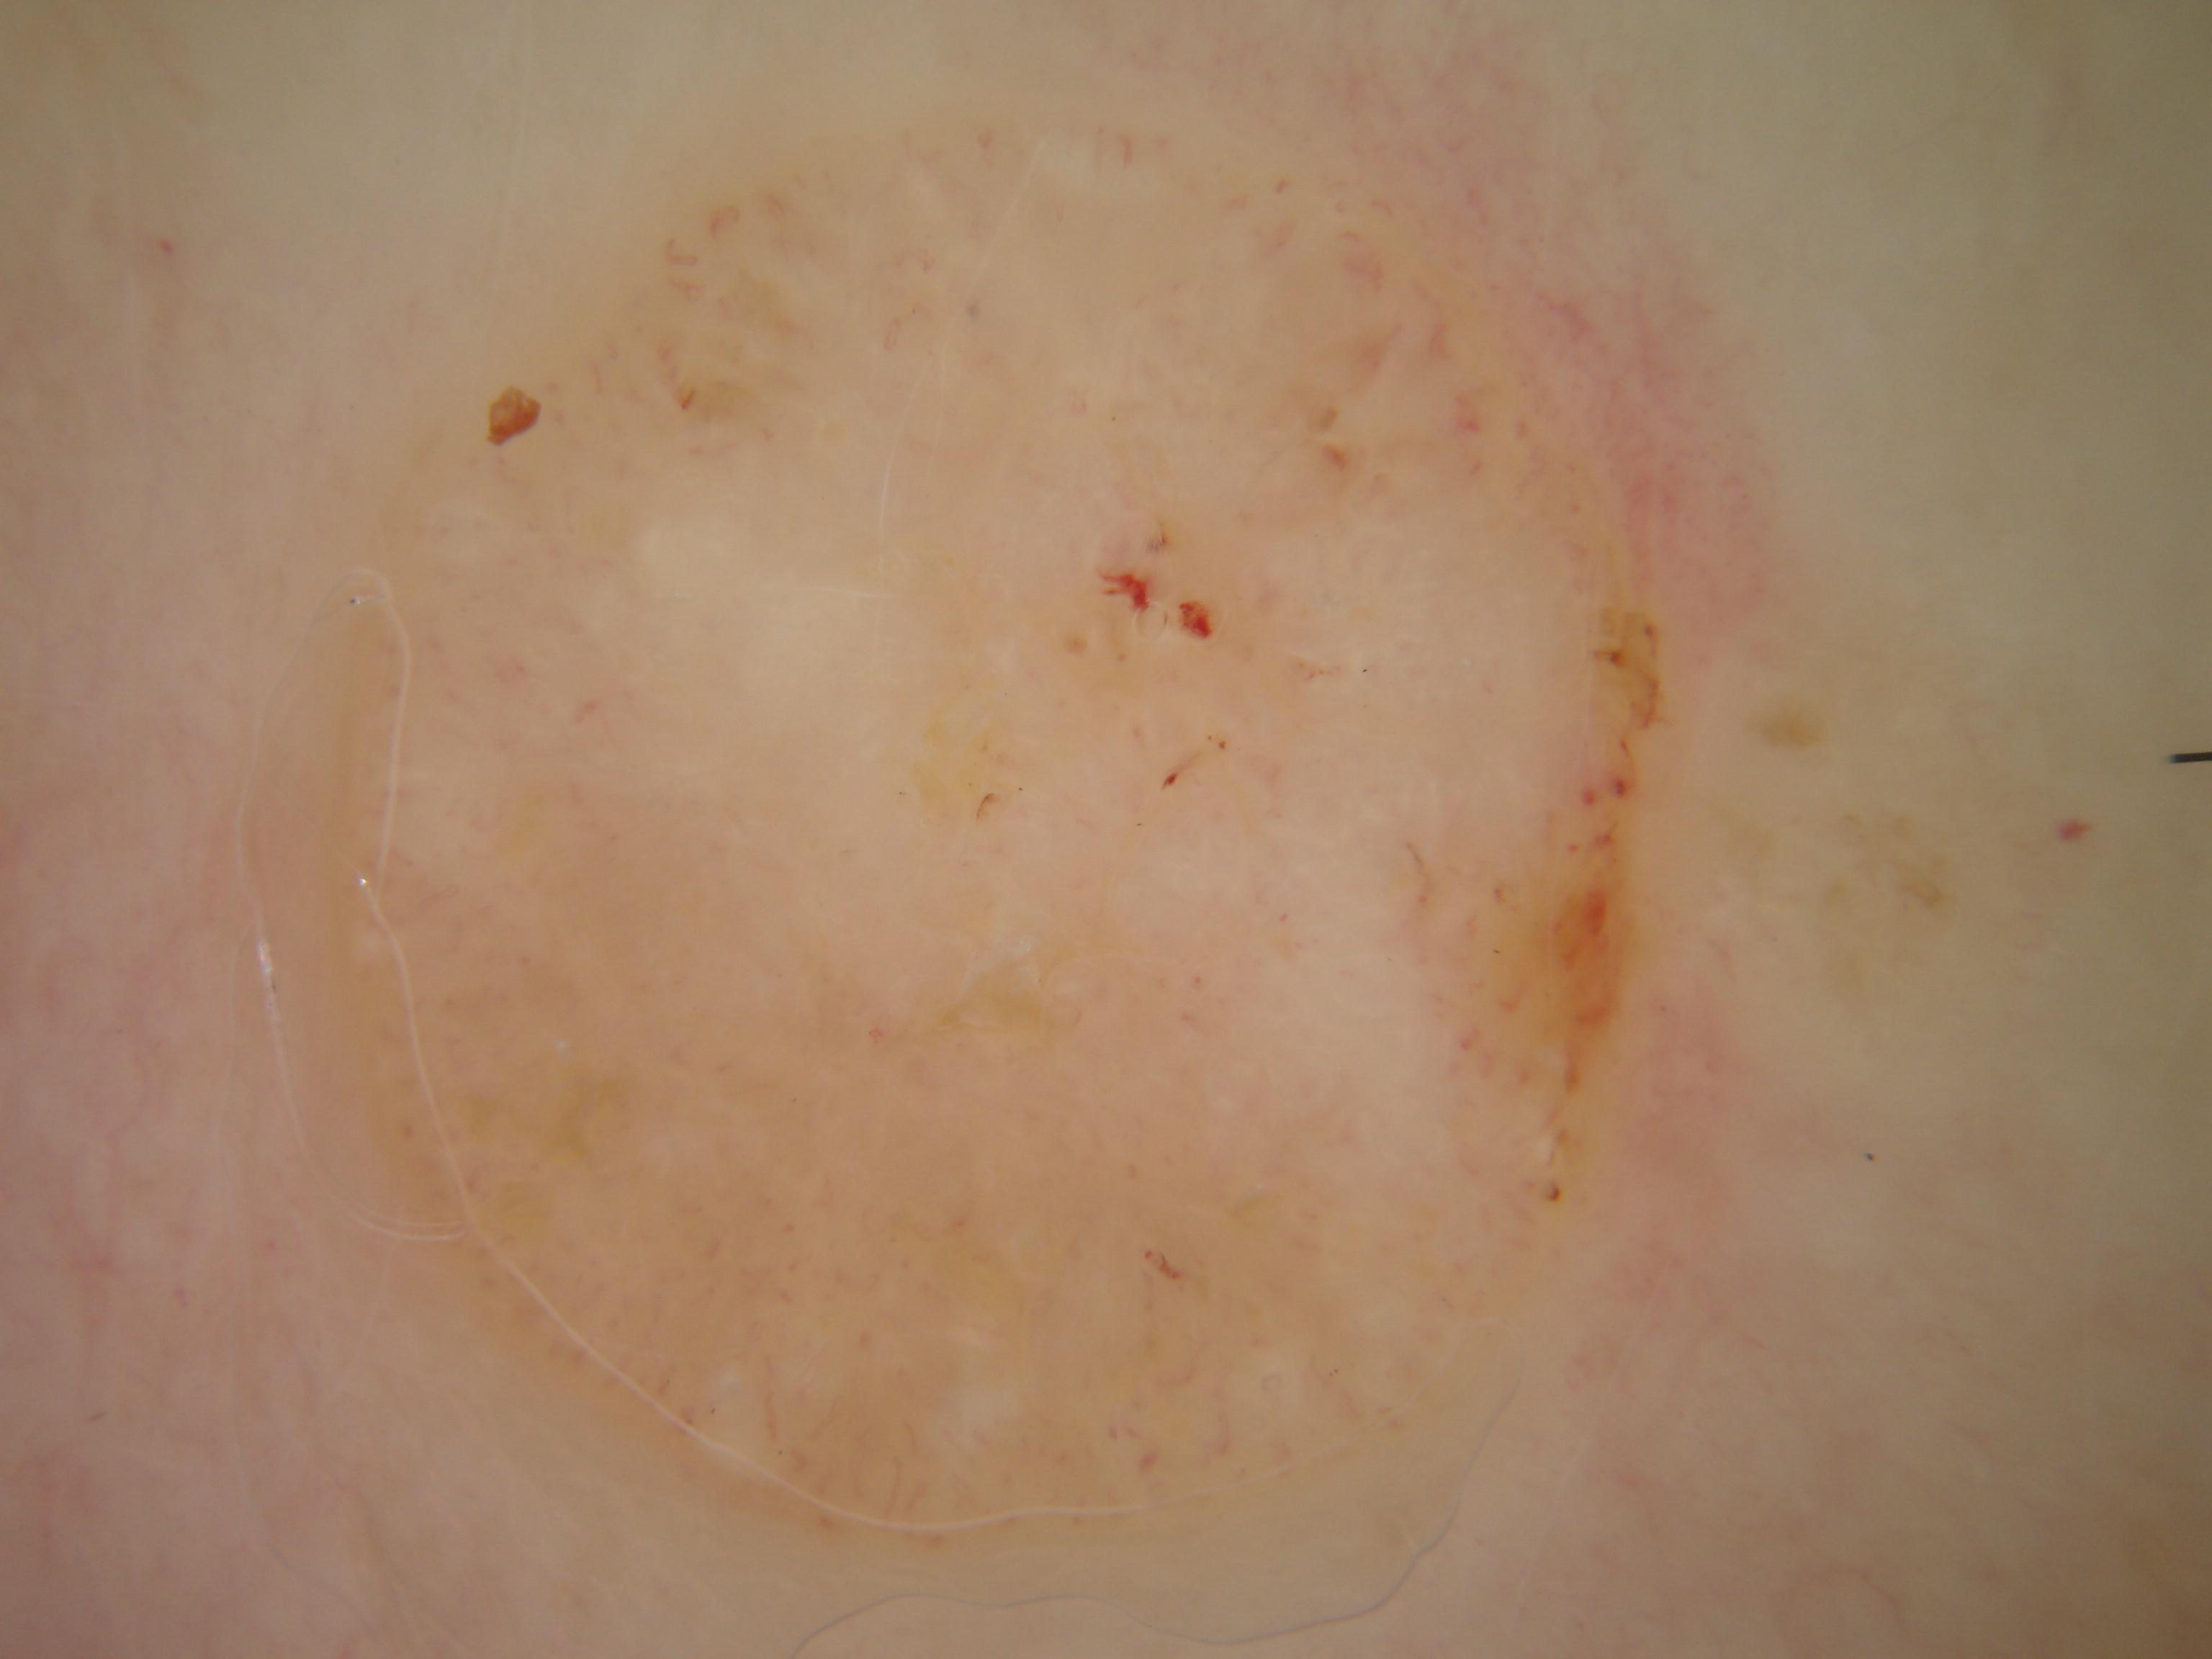

{

"age_approx": 50,

"anatom_site_general": "posterior torso",

"concomitant_biopsy": true,

"dermoscopic_type": "non-contact polarized",

"diagnosis_1": "Malignant",

"diagnosis_2": "Malignant adnexal epithelial proliferations - Follicular",

"diagnosis_3": "Basal cell carcinoma",

"diagnosis_confirm_type": "histopathology",

"family_hx_mm": false,

"image_type": "dermoscopic",

"melanocytic": false,

"patient_id": "IP_2559011",

"personal_hx_mm": false,

"sex": "female"

}